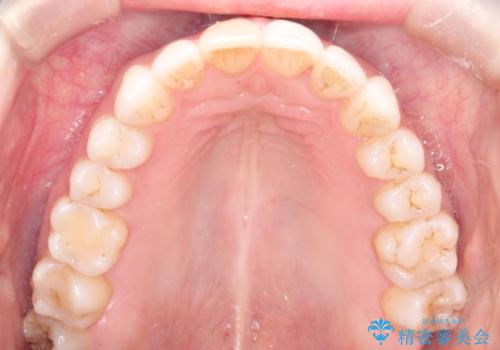

インビザラインによる非抜歯での八重歯の矯正

- 左上の八重歯と、上の歯のがたつきを主訴に来院されました。

上の奥歯を後方に移動させてスペースを作るのと、歯と歯の間をわずかに削り歯を並べる計画としました。

非常に強力的な患者様であったので、上下の正中も合わせ、ガタガタも改善することができました。